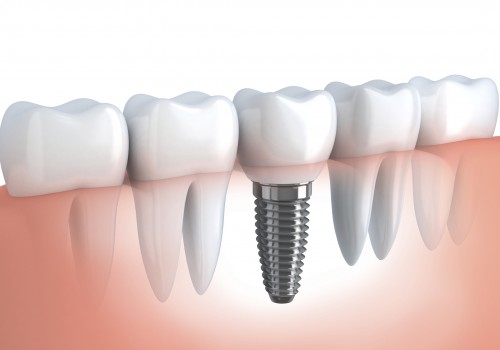

Implantes

A implantodontia é uma especialidade que evoluiu tanto nos últimos anos, que hoje não...

A implantodontia é uma especialidade que evoluiu tanto nos últimos anos, que hoje não há mais...